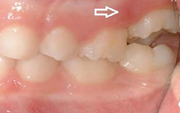

Ravijärgne seis. Jäävhammas on täielikult lõikunud.

) Röntgenülesvõte. Ülemise esimese jäävmolaari lõikumine on takistatud 2. piimamolaari tõttu

Esimese jäävmolaari ektoopiline lõikumine